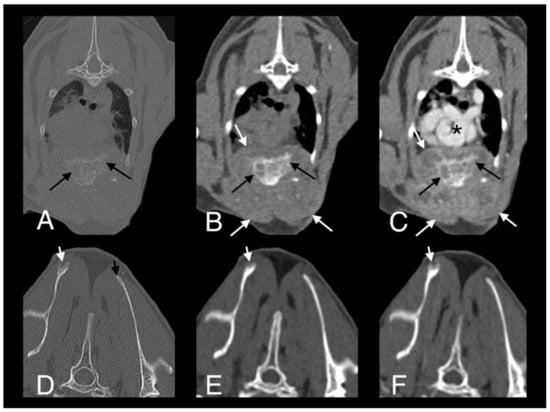

- Bennett, A.D.; Lalor, S.; Schwarz, T.; Gunn-Moore, D.A. Radiographic findings in cats with mycobacterial infections. J. Feline Med. Surg. 2011, 13, 718–724. [Google Scholar] [CrossRef] [PubMed]

- Major, A.; Holmes, A.; Warren-Smith, C.; Lalor, S.; Littler, R.; Schwarz, T.; Gunn-Moore, D. Computed tomographic findings in cats with mycobacterial infection. J. Feline Med. Surg. 2016, 18, 510–517. [Google Scholar] [CrossRef]

- Major, A.; O’Halloran, C.; Holmes, A.; Lalor, S.; Littler, R.; Spence, S.; Schwarz, T.; Gunn-Moore, D. Use of computed tomography imaging during long-term follow-up on nine feline tuberculosis cases. J. Feline Med. Surg. 2018, 20, 189–199. [Google Scholar] [CrossRef]

- Lalor, S.M.; Clark, S.; Pink, J.; Parry, A.; Scurrell, E.; Fitzpatrick, N.; Watson, F.; O’Halloran, C.; Gunn-Moore, D. Tuberculosis joint infections in four domestic cats. JFMS Open Rep. 2017, 3, 1–8. [Google Scholar] [CrossRef]